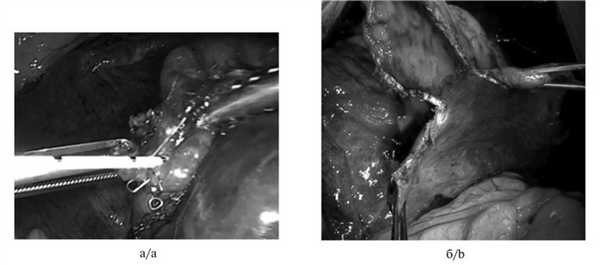

Вентиляционный способ. После пересечения сегментарного бронха в просвет дистальной культи бронха вводили катетер Фолея соответствующего диаметра, раздували манжетку (рис. 2, а).

Рис. 2. Интраоперационные фотографии вентиляционной методики определения межсегментарных границ. а — инсуффляция воздуха в просвет сегментарного бронха через катетер Фолея, б — разметка границы удаляемого сегмента, заполненного воздухом. Удерживая катетер пинцетом или мягким зажимом для предотвращения дислокации в просвет бронха, по каналу катетера производили инсуффляцию воздуха посредством инсуффлятора, шприца Жане или медицинской груши. Расправляясь, наполненный воздухом сегмент приобретал розовую окраску, более светлую по сравнению с окружающей ателектазированной легочной тканью. При этом определялась четкая инфляционно-дефляционная линия, соответствующая межсегментарной плоскости (см. рис. 2, б).

При торакоскопической сублобарной анатомической резекции легкого межсегментарную границу определяли путем инсуффляции воздуха в удаляемый сегмент легкого шприцем через длинную эндоскопическую иглу, введенную тангенциально в просвет дистальной культи предварительно пересеченного и прошитого эндоскопическим сшивающим аппаратом сегментарного бронха (рис. 3).

Рис. 3. Интраоперационные фотографии вентиляционной методики определения межсегментарных границ при торакоскопии. a — инсуффляция воздуха через иглу, введенную в просвет прошитого сегментарного бронха, б — разделение легочной паренхимы коагулятором в соответствии с разметкой границы сегмента.